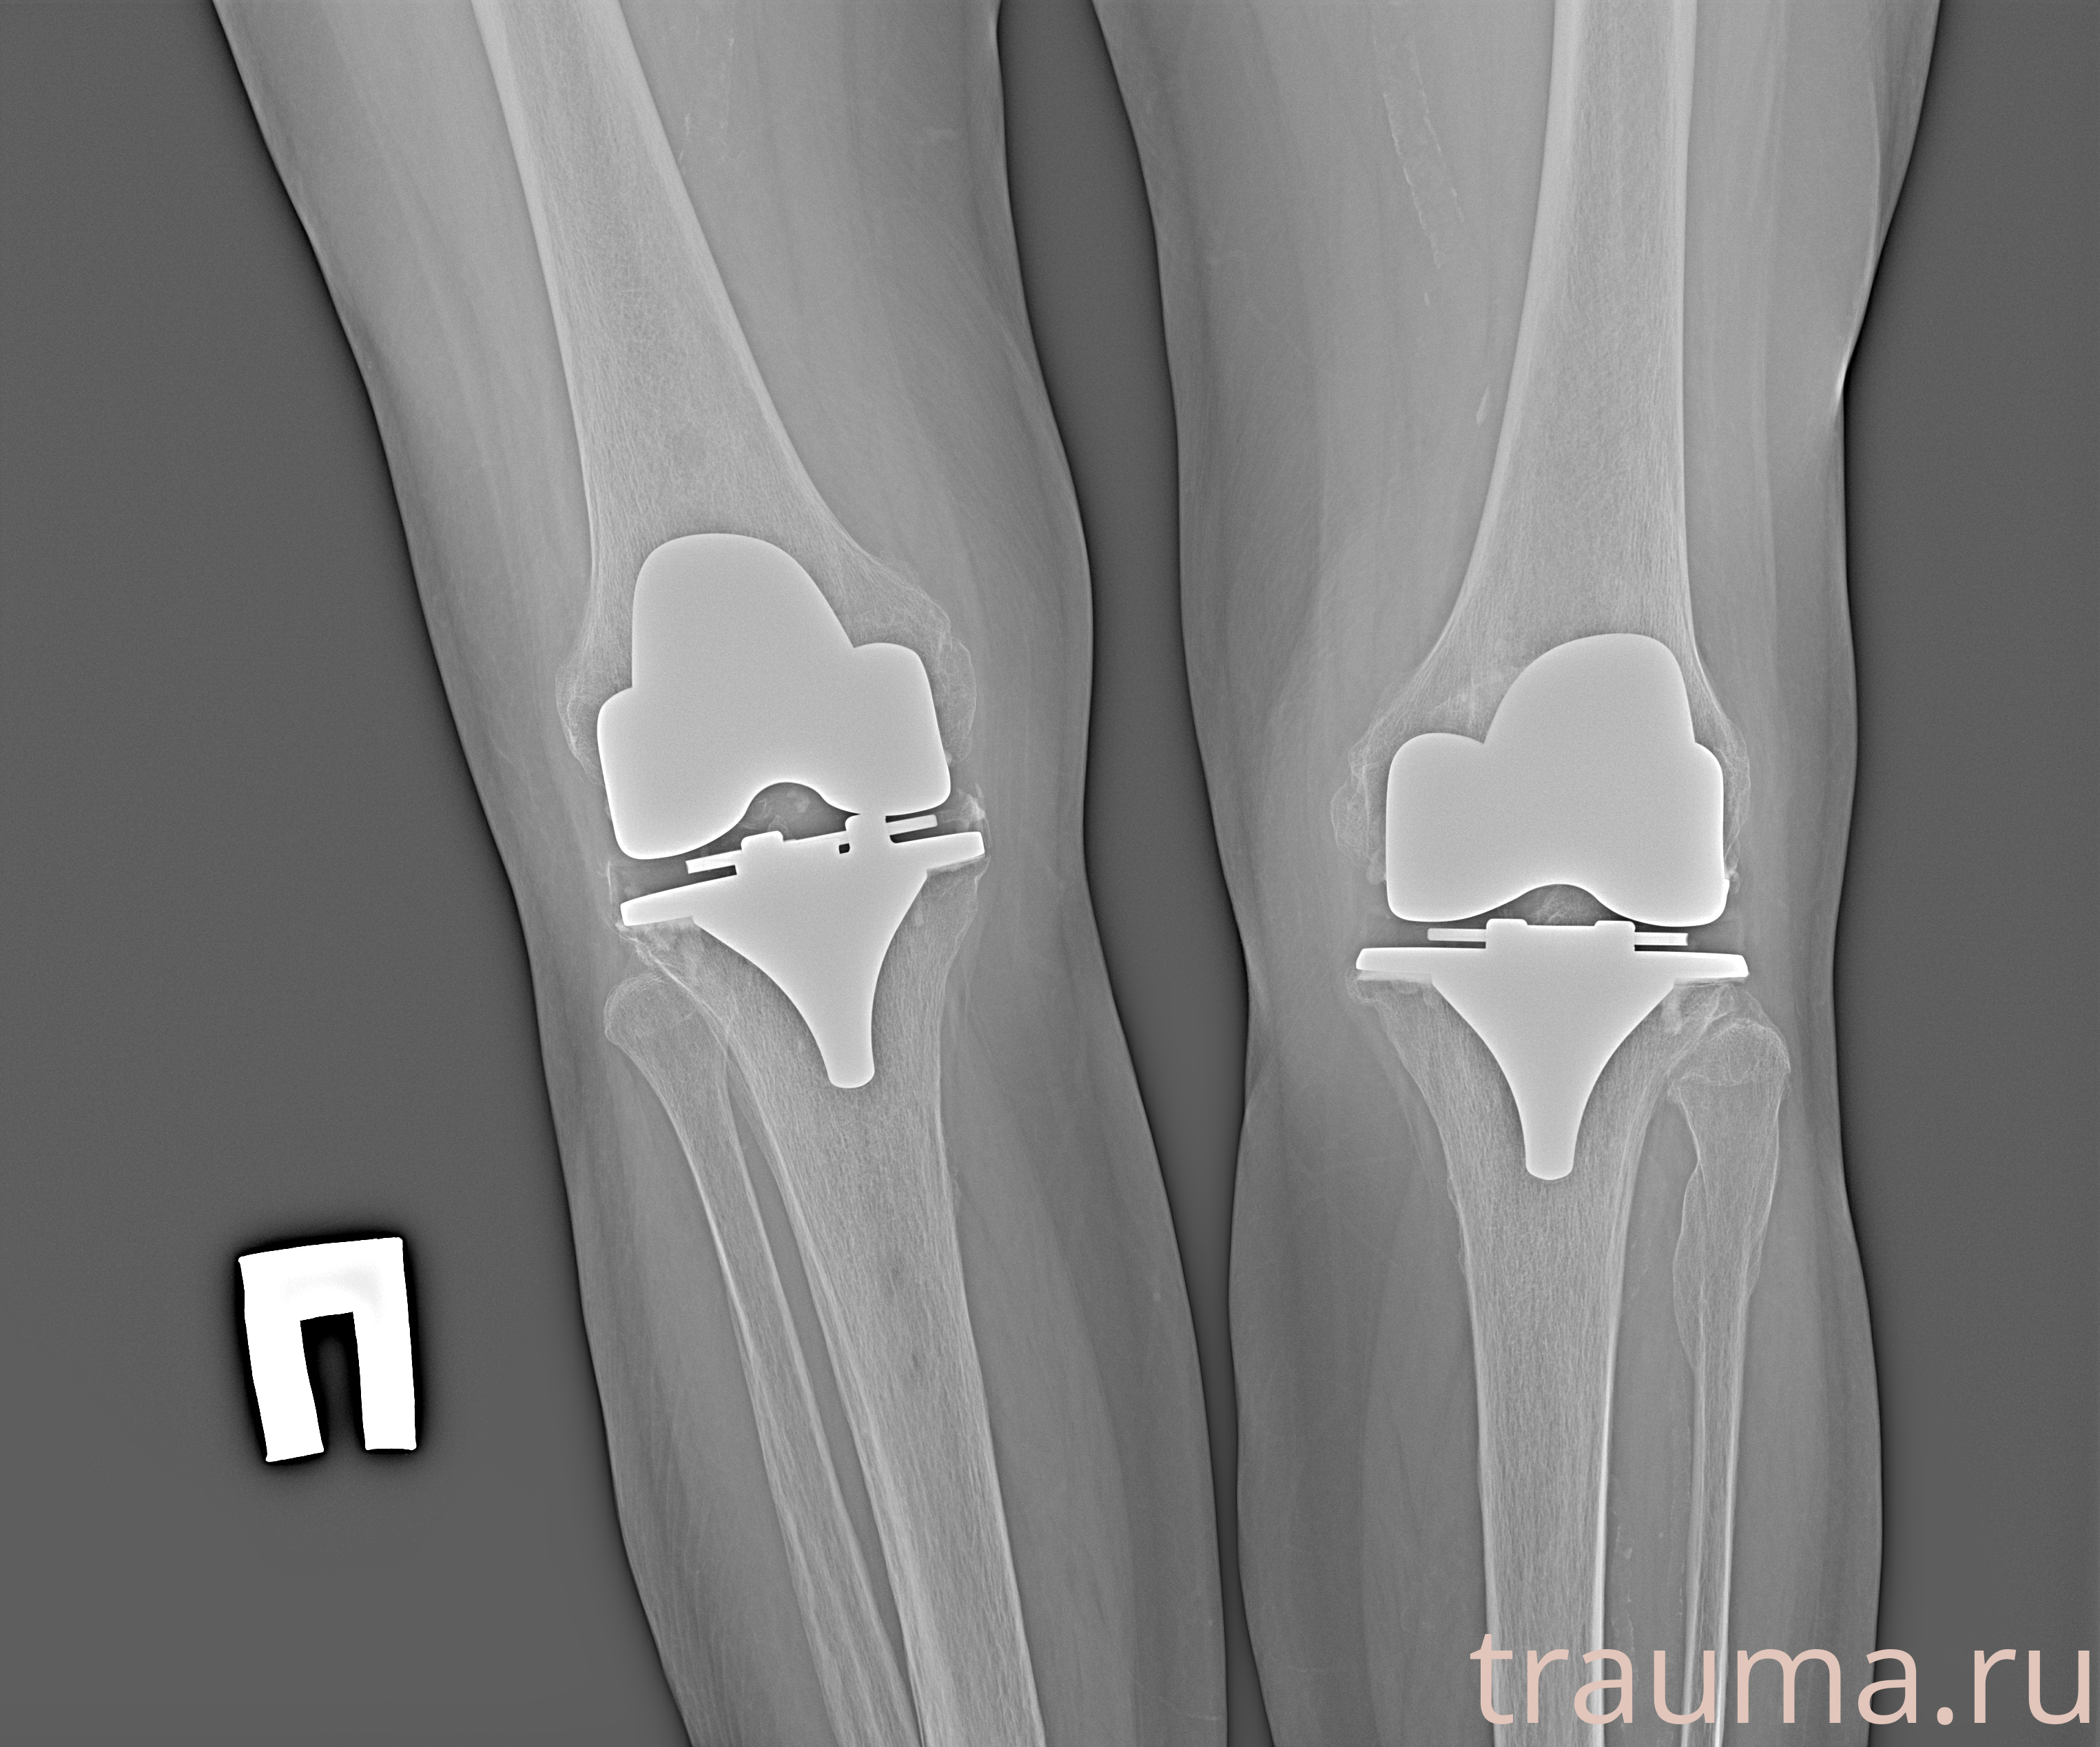

Рентгенограммы

Рентген на дому: по вашему адресу приезжает врач-рентгенолог, травматолог-ортопед с мобильным рентгеновским аппаратом, проводит диагностику травмы или заболевания, делает необходимые рентгенограммы, дает рекомендации по дальнейшему лечению. Получить качественные снимки в домашних условиях возможно благодаря уникальной методике, разработанной МосРентген Центром для института  Склифосовского